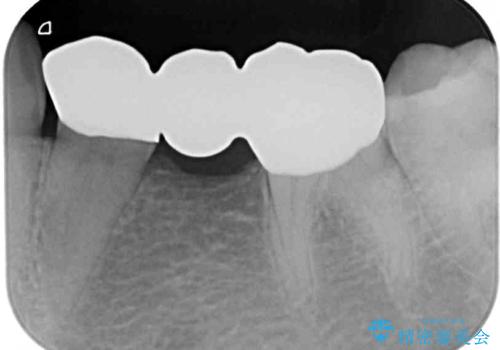

抜歯してからインプラント埋入までには時間がかかるため、その間に下顎左右臼歯の金属のブリッジをオールセラミックへ変えていくこととしました。

目立つ部分の銀歯や気になる変色歯をまとめてきれいに仕上げることができました。